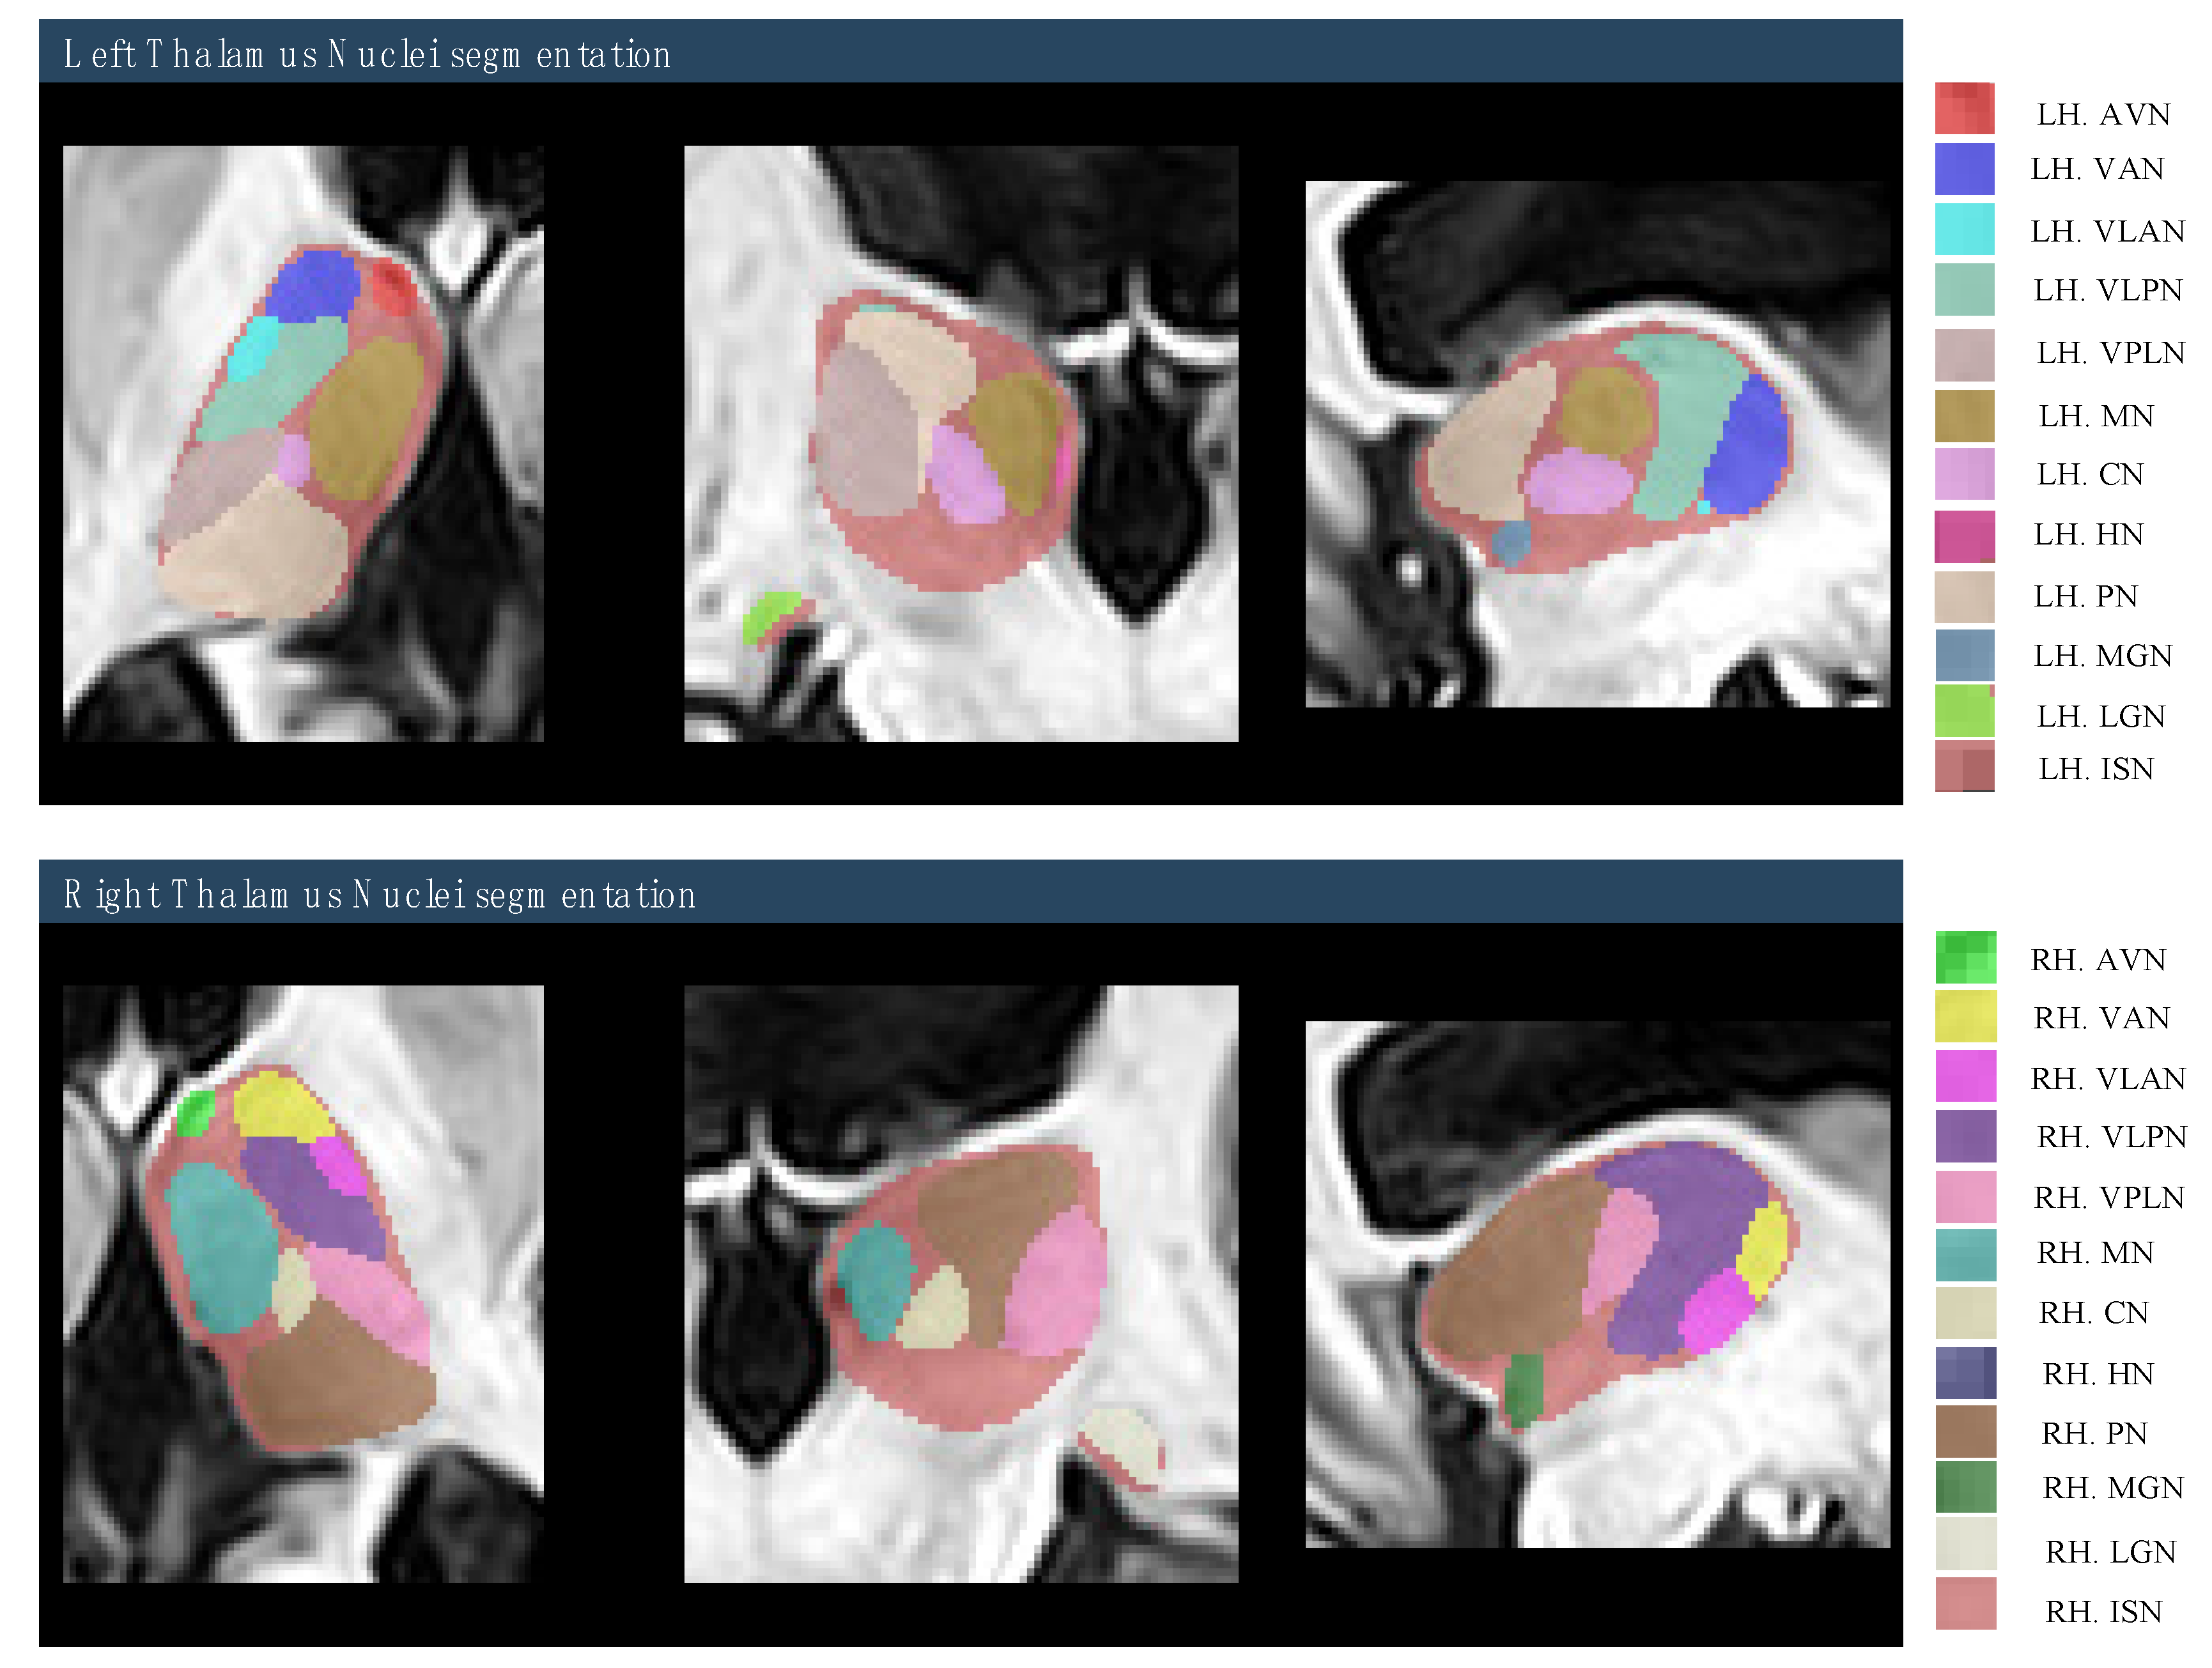

2.4. Region of Interest (ROI) Selection

- Manjón, J.V.; Coupé, P. volBrain: An Online MRI Brain Volumetry System. Front. Neuroinformatics 2016, 10, 30. [Google Scholar] [CrossRef]

- Niemann, K.; Mennicken, V.; Jeanmonod, D.; Morel, A. The morel stereotactic atlas of the human thalamus: Atlas-to-MR registration of internally consistent canonical model. NeuroImage 2000, 12, 601–616. [Google Scholar] [CrossRef]